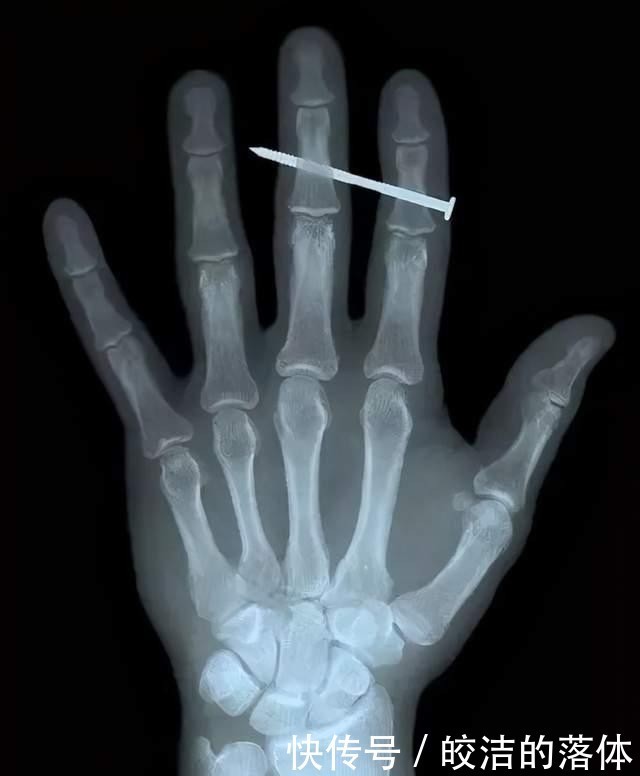

它能透射常见物体,包括人体,但在肌肉和骨骼透射率不一样,所以就会系形成阴影,负片就是就是高亮色,因此我们看到的X射线照片其实就是负片,亮的地方透过率低,一般骨折或者局部钙化或者纤维化等都会影响透射率,X光是最常见的医疗检查。